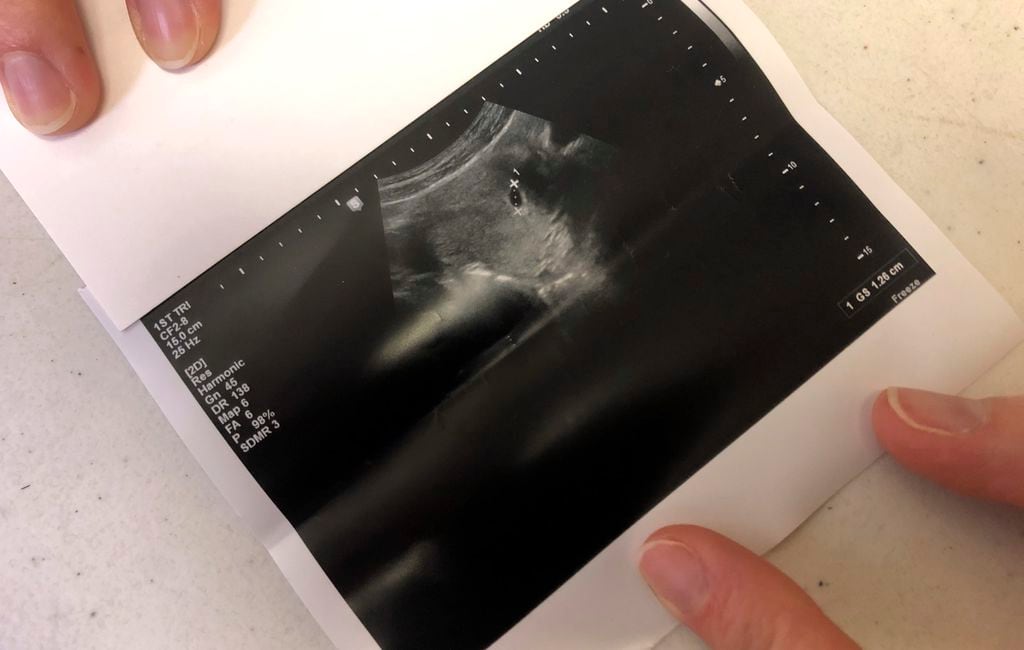

State Micaiah Bilger Jun 17 2020 914AM Des Moines IA. Planned Parenthood Takes Aim at Indiana Ultrasound Law Tim Bradley November 16 2016. Doctors in Planned Parenthood and other abortion clinics use ultrasounds to determine the age and size of the baby or to guide them as they perform abortions.

A federal judge heard arguments on November 9 on Planned Parenthoods challenge to an Indiana law requiring that an ultrasound be performed on a woman seeking an abortion at least 18 hours before the abortion is scheduled to take place. From the information I have read Planned Parenthood uses ultrasound for the abortion procedure they will not perform an ultrasound for someone wantingintendingconsidering keeping their baby. No they do not.

Planned Parenthood says they provide ultrasounds but the ultrasounds are really just used to facilitate abortions. FORT WAYNE Ind. We will only give you an ultrasound if you want an abortion.

Planned Parenthood uses ultrasound to determine a babys age and position in the womb before it kills her. They rarely use them otherwise. ADVERTISEMENT The abortion business is criticizing an Iowa bill that ensures abortion facilities give women the opportunity to see their unborn babies on an ultrasound and hear their babys heartbeat at least 24 hours prior to.

Only three of the 68 Planned Parenthood centers visited by Live Action investigators were able to provide women with an ultrasound for a purpose other than abortion. You can visit your local Planned Parenthood health center for free or low-cost ultrasounds whether or not you have insurance.

But when looking at Planned Parenthoods website a pregnant woman seeking care would. At Planned Parenthood Live Action investigators discovered ultrasound machines generally only have one purpose. Planned Parenthood continues to perpetuate the myth that it offers the comprehensive healthcare women need not simply abortions. Your doctor might also be able to help you find affordable ultrasounds in your area. Only 3 said theyd check the health of the baby. Planned Parenthood staff admitted things like We dont do any ultrasounds for prenatal care. 2 days agoPlanned Parenthood alone provided over 345672 abortions in one year Oct. A new Live Action video released in the Planned Parenthood. They rarely use them otherwise.

The Abortion Corporation investigation further proves that the abortion chain exists primarily to commit. Planned Parenthood says they provide ultrasounds but the ultrasounds are really just used to facilitate abortions. Only 3 said theyd check the health of the baby. We give information about the importance of prenatal care and how to connect with a prenatal care provider. A new Live Action video released in the Planned Parenthood. CNS Ending three years of legal dueling Indiana Attorney General Curtis Hill announced Aug. Part of that investigation revealed that Planned Parenthood doesnt provide ultrasounds to women unless those women have decided to abort.